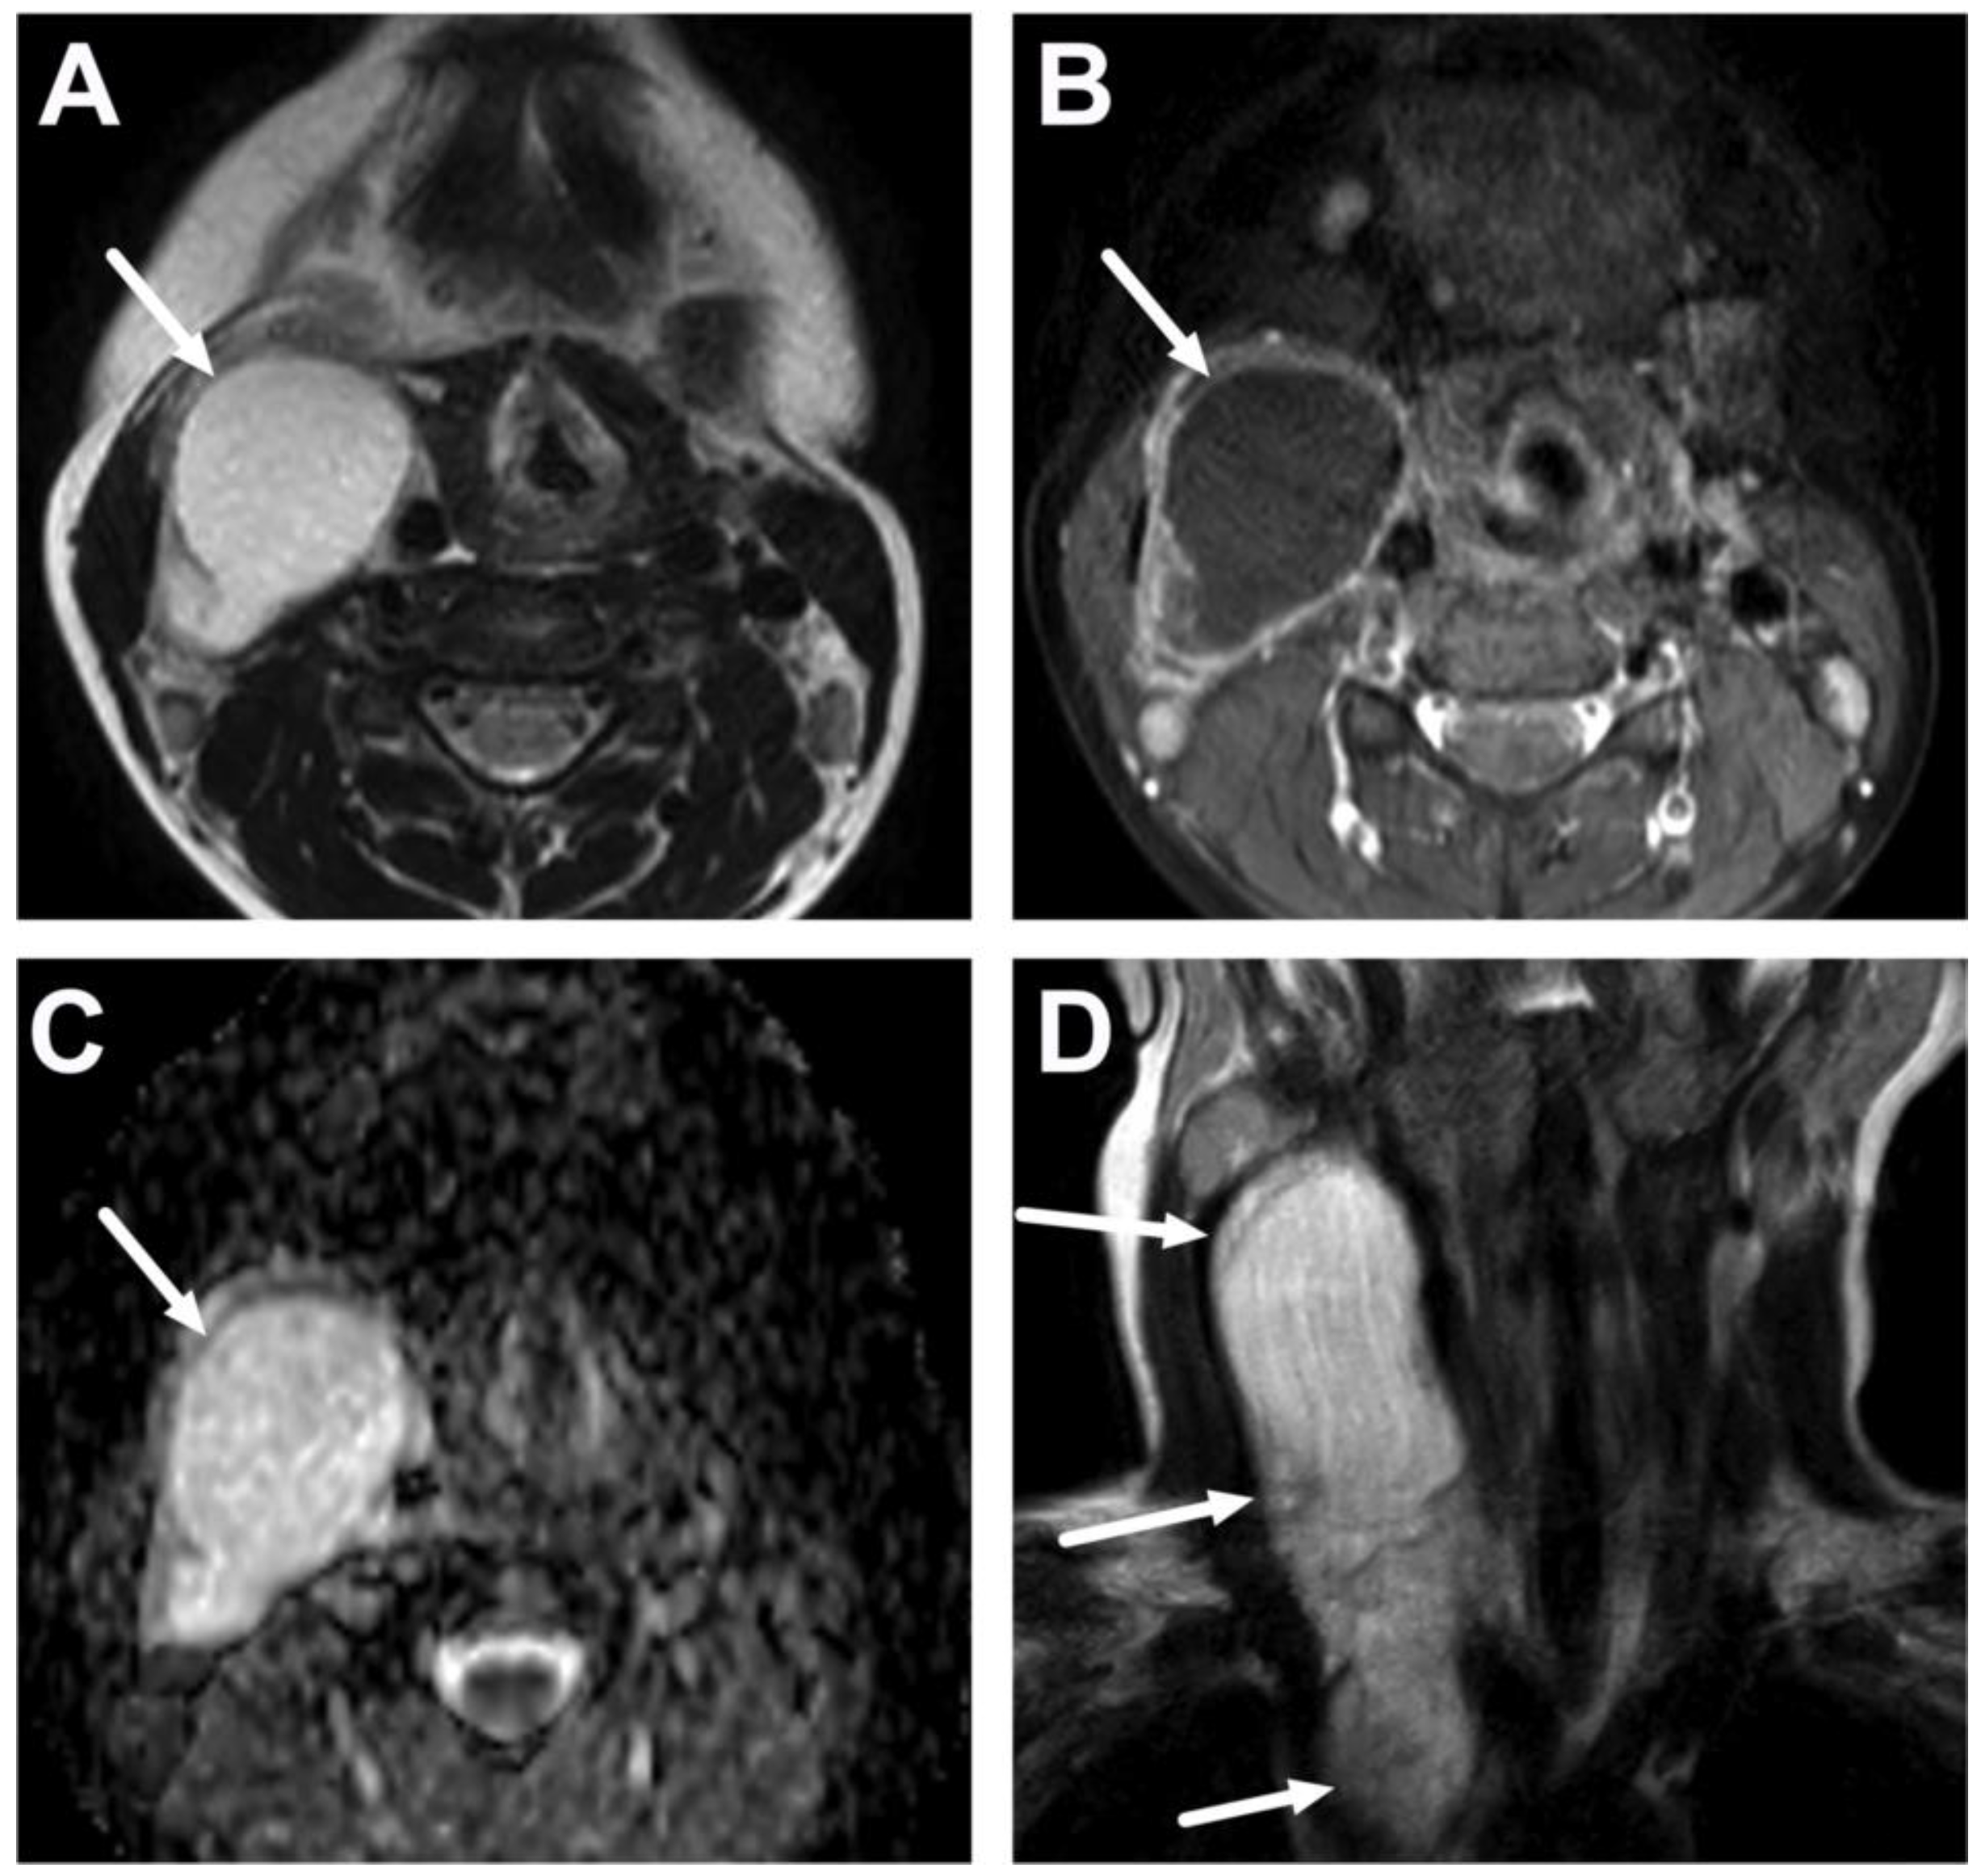

6.1. Mediastinitis

| Complications | Whole protocol | Abscess extending to multiple deep neck spaces, mediastinis, venous thrombosis, and airway compromise. | Detection of potentially life-threatening conditions. | Magnetic resonance angiography (MRA) or CECT may be needed to diagnose venous thrombosis; defining airway compromise is difficult. |